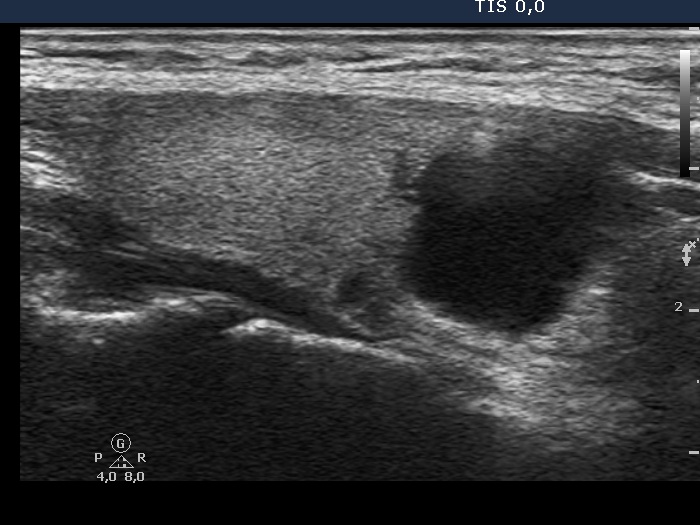

First examination (1st row of images)

Clinical presentation. An 18-year-old woman requested a screening because her mother was operated on a multinodular goiter. She had no complaints.

Palpation: no abnormality.

Ultrasonography. The thyroid was echonormal. There was a cystic lesion in the lower-dorsal part of the right lobe.

3 mL watery fluid was aspirated. There were no cells on the smear. The parathormone level of the cystic fluid was 495 pg/mL.

Functional state: both the thyroid and the parathyroid functions were normal - TSH 1.06 mIU/L, parathormone level 22 pg/mL (normal value: 15-65).

Combined cytological-clinical-sonographic diagnosis: parathyroid cyst.